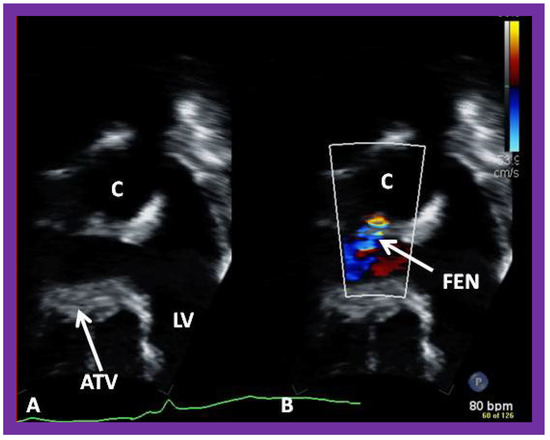

Surgically created fenestrations (Figure 50, Figure 51, Figure 52 and Figure 53) can also be demonstrated by color Doppler studies and the mean gradient across the fenestration (Figure 52 and Figure 53) is helpful in determining the physiologic state; a mean gradient of 4 to 8 mmHg is considered adequate.

Article Metrics

Back to TopTop